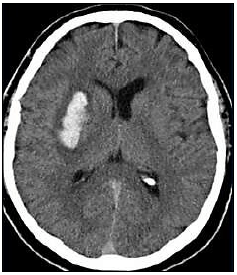

Paciente, sexo masculino, 59 anos, apresenta quadro súbito de hemiparesia completa e proporcionada em dimídio esquerdo, associada à disartria e desvio de rima labial para a direita. Admitido em pronto atendimento hospitalar, realizou a seguinte tomografia computadorizada de crânio:

Qual a etiologia mais provável desse AVC hemorrágico?